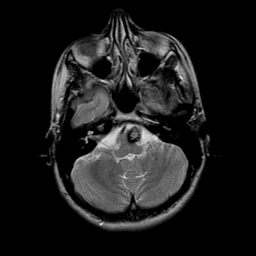

overlay -- Slice #5

[Home][Help][Clinical] Slice 5

Click on sagittal image to select slice. Click on thin tickmark to change timepoint, or thick tickmark for overlay.